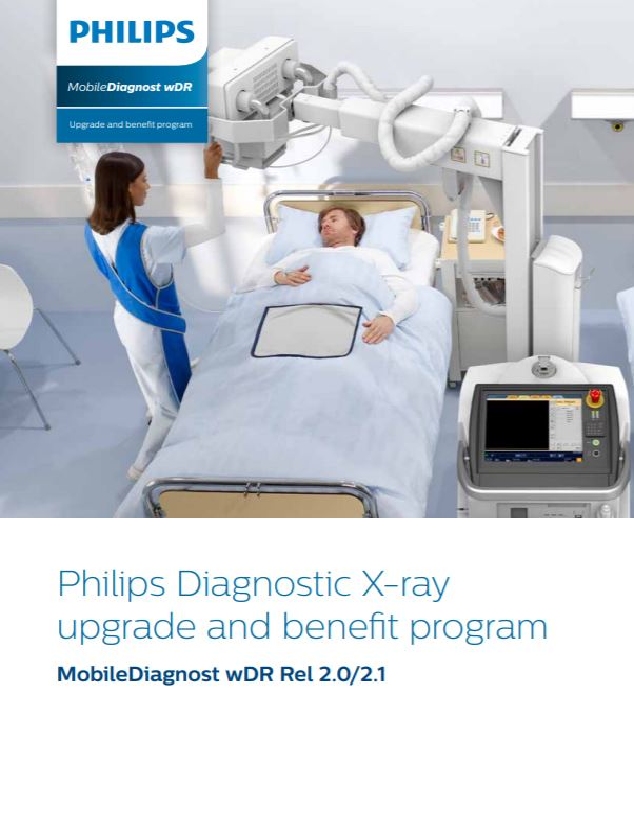

MobileDiagnost wDR Rel 2.0/2.1